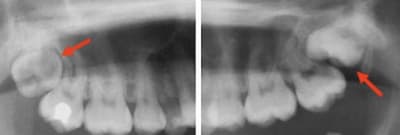

Bah alors ! Ben bien entendu qu’il faut les laisser en place ! Ça ne cause aucun problème...

8DE0A1E8-2DD0-4D53-A097-9BB4EBF20214_c1hzlx.jpg

AC10A55A-5FE5-4EEF-8BC3-48CE8E842DE0_wmi4kc.jpg

AB108EDA-34AF-4F84-AF10-998952ADDB29_ul6tfn.jpg

8243588C-A2F4-4BDC-B073-E1B3D70BBDF4_ok8qx5.jpg

E561E138-B7BA-4F34-AC1D-E238600B02A9_w4mrpg.jpg

27A0EF84-30D2-474C-B7F5-DD3F605A0909_zd09jn.jpg

ED7428F9-3851-4AF0-BDDB-192CED35661C_rcvw5y.jpg